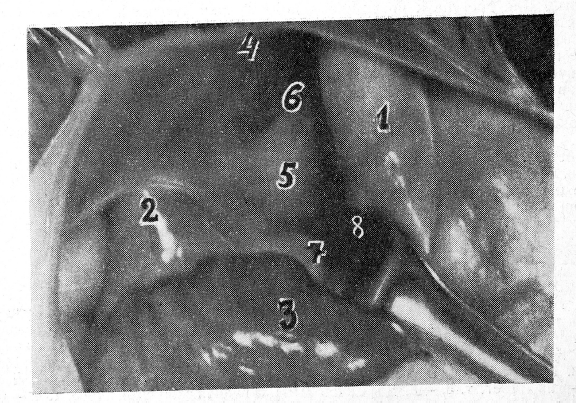

Левый сердечно-перикардиальный промежуток (аорто-венозный) выявляют после отведения сердца вправо. Для того чтобы не было перегиба сосудистого корня сердца, угол между левым предсердием и боковой стенкой перикарда должен составлять 80— 90°. Этого промежутка вполне достаточно для подхода к левому бронху. Промежуток ограничен справа левым предсердием, слева перикардом, сверху начальной частью дуги аорты, снизу верхней и нижней левыми легочными венами. Книзу промежуток переходит в диафрагмальную площадку левого желудочка и косой синус (рис. 4). Длина промежутка 6—8 см, ширина — 2,5—3,0 см.

Внешними ориентирами, которыми должен руководствоваться хирург при подходе к бронху, служат: левая легочная артерия, верхний перикардиальный карман и левые легочные вены. Наши диоптрографические данные показывают, что левая легочная артерия соответствует начальному отделу левого главного бронха. Между левой легочной артерией и верхней левой легочной веной расположено углубление — верхний перикардиальный карман. В него открывается левое отверстие поперечного синуса. Часто оно отграничено от кармана складкой Маршалла. Когда сердце лежит в своем ложе, то в кармане помещается левое ушко предсердия. Верхний перикардиальный карман соответствует среднему отделу левого главного бронха.

Верхняя левая легочная вена хорошо видна, и ее положение характеризует дистальный конец левого главного бронха и его деление на долевые бронхи. Нижняя левая легочная вена соответствует начальному отделу нижнего долевого бронха.

Рис. 4. Левый сердечно-перикардиальный промежуток (аорто-венозный):

1 — конечный отдел восходящей аорты; 2 — левая легочная артерия; 3 — верхний перикардиальный карман; 4 — складка Маршалла; 5 — верхняя левая легочная вена; 6 — нижняя левая легочная вена; 7 — левое предсердие с левым ушком; 8 — левая боковая стенка перикарда; 9 — левый вход в поперечный синус.